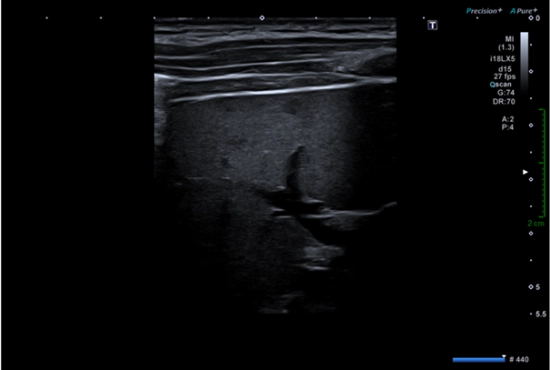

Quand des "tendinopathies achilléennes" cachent un piège poplité : l’importance de l’échographie dynamique et de l'examen clinique concomitant